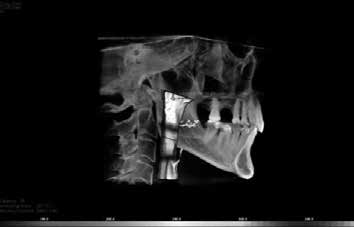

There were no positive findings for muscle, tendon and ligament palpation. Imaging utilizing CBCT (cone beam computed tomography) demonstrated a significant cant of the mandible to the left side (affected side) and was confirmed with photograph of patient with tongue blade, see Figures 6 and 7. This indicates that the elevator muscles or muscles of mastication are shorter on the left than right. When muscles are shorter than their resting length they have greater resting tonus or tension.

Nasal obstruction was observed from the iCAT CBCT, with deviation of the septum to the left with nasal soft tissue hypertrophy, see Figure 8. The oropharyngeal airway appeared to be within normal dimensions while awake, however it did not measure how much it can collapse while asleep, see Figure 9.